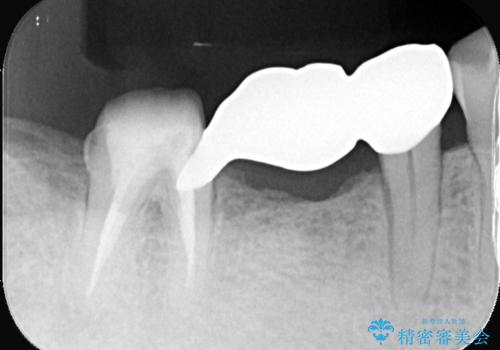

- 主訴:右下のセラミックのブリッジが何度も同じところで折れて壊れてしまう。

対合歯との咬合関係において、右下7番目と6番目の被せものの連結部がたわみやすい環境にあったため、ブリッジの新製ではなくインプラント治療を行いすべての歯を単冠仕上げとすることにしました。

何度も右下6、7間でブリッジが折れてしまうとのことでした。対合歯とブリッジの連結部が強く当たりたわみやすい状態でした。破折しずらい金属を使用したブリッジの選択もありましたが、支台歯(右下7)が失活歯場合、破折リスクが高く、破折してしまった場合にまたブリッジを外しての再治療になってしまう可能性を説明したところ、全て単冠仕上げとできるインプラント治療を希望されました。